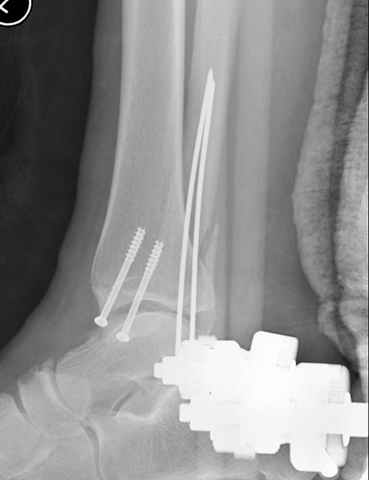

A propos fibular fixation if one is eager to stabilize it separately. In the fracture pattern a way of closed fixation by V-shaped stressed wire (advanced by colleagues from Moscow, prof. Lazarev A.F. et al.) must be excellent. We use indirect closed reduction by the external fixator. Example attached, that fibular fracture is even more suitable for plating but the wire did the job.

I didn't perform stress tests, at least it prevents fibula against secondary displacement. Stressed 2 mm double wire is not so weak.

I used it only in two fibular cases recently. Colleagues from Moscow use the wires mostly for proximal humerus and even femoral neck.

Идея хорошая, особенно если короткий и поперечный перелом. Узнал о методе на прошлогодней конференции в Санкт Петербурге, доклад от ЦИТО,

и в доказательство Александр показал на своих снимках оригинальность метода, концепция "сделай сам имплант" из малого разреза и доступность. (при совершенствовании методики и инструментарии, метод может быть применен и в других случаях)